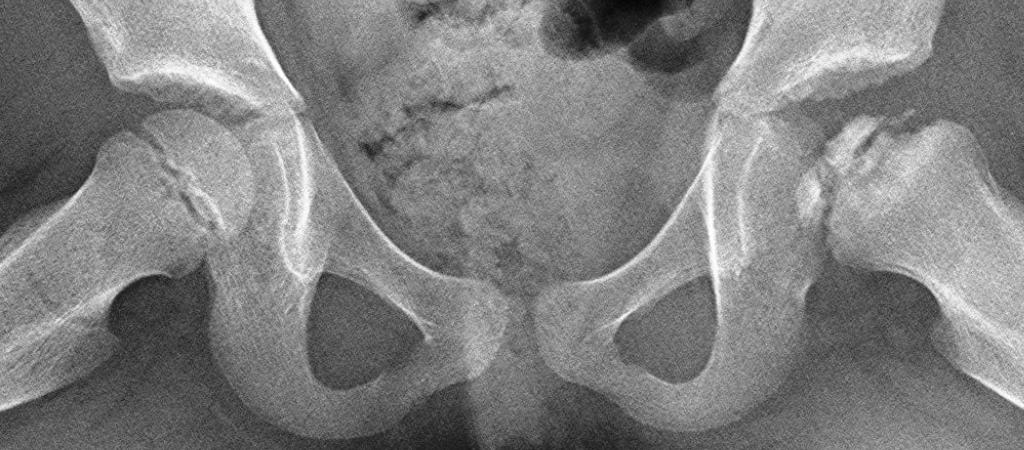

La enfermedad de Perthes afecta a la cadera infantil. Es una necrosis en la cabeza del fémur causada por la falta de riego sanguíneo. Se presenta más en varones (por cada 4 niños, 1 niña), entre 3 y 12 años pero con una mayoría en torno a los 6-8 años. En ocasiones puede ser bilateral. El síntoma más común es la cojera, restricción de movimiento, dolor de rodilla, muslo o ingle. Si tu hij@ tiene alguno de estos síntomas, acude a un traumatólogo infantil para que le explore. HAZTE SOCIO. En ASFAPE te ofrecemos información actualizada y contacto con otras familias con las que compartir experiencias, además de diferentes eventos con expertos en Perthes. Aunque un gran porcentaje de casos evolucionan bien, es una enfermedad que dura varios años, una enfermedad poco frecuente, de causa desconocida y que en ocasiones puede dejar secuelas en la vida adulta.